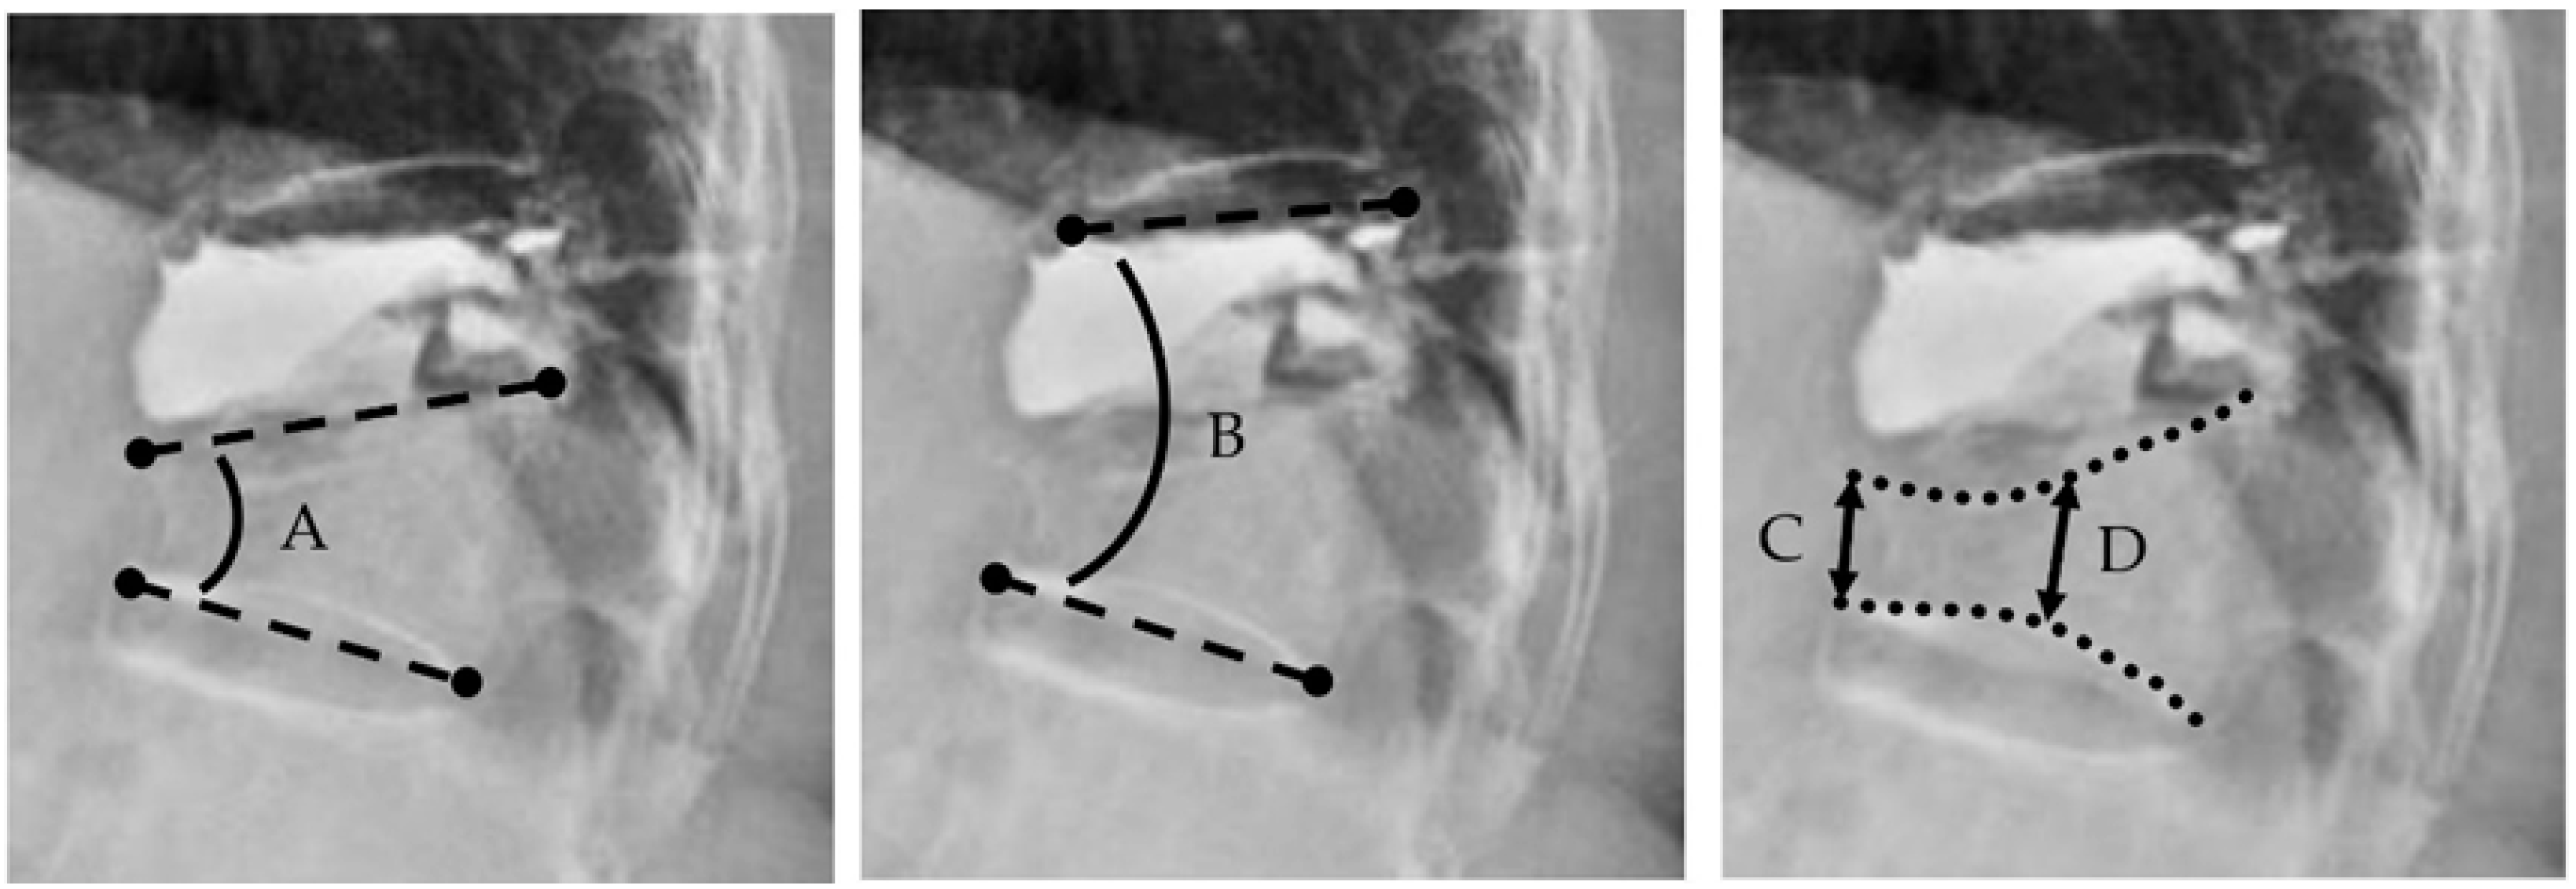

| Single kyphotic angle ‡ | 13.4 ± 9.7 | 8.6 ± 7.0 | 10.3 ± 9.1 | <0.01 | 0.05 |

| Two-segment kyphotic angle § | 15.6 ±11.8 | 12.6 ± 10.0 | 15.2 ± 10.1 | 0.02 | 0.03 |

| Anterior vertebral body height | 1.9 ± 0.7 | 2.2 ± 0.6 | 2.3 ± 0.6 | <0.01 | 0.2 |

| Mid vertebral body height | 1.7 ± 0.5 | 1.9 ± 0.5 | 1.9 ± 0.5 | <0.01 | 0.8 |